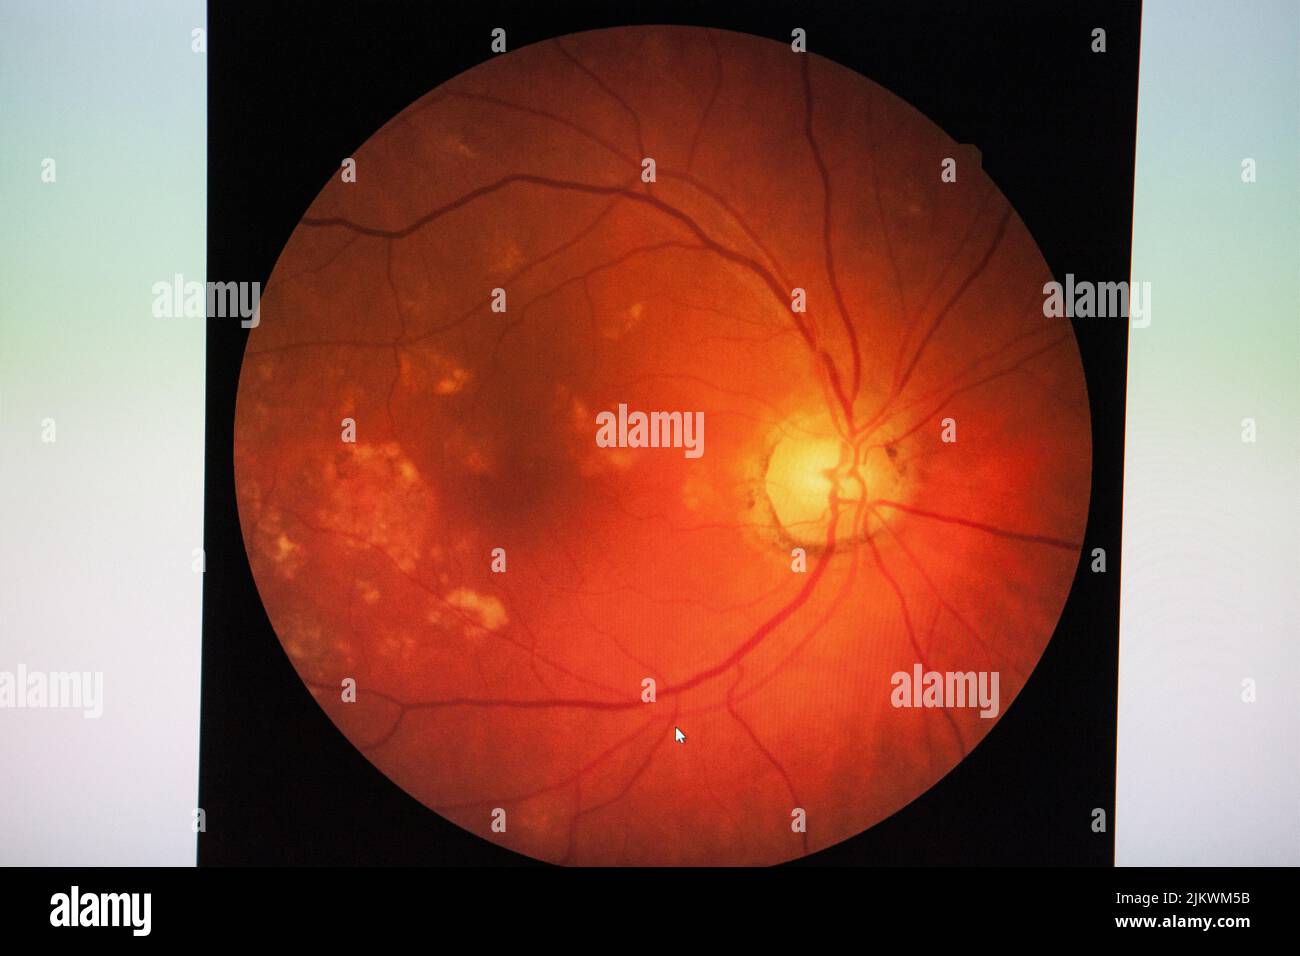

Fundus: routine examination established by an ophthalmoscope to check the health of the eye. Stock Photohttps://www.alamy.com/image-license-details/?v=1https://www.alamy.com/fundus-routine-examination-established-by-an-ophthalmoscope-to-check-the-health-of-the-eye-image476923031.html

Fundus: routine examination established by an ophthalmoscope to check the health of the eye. Stock Photohttps://www.alamy.com/image-license-details/?v=1https://www.alamy.com/fundus-routine-examination-established-by-an-ophthalmoscope-to-check-the-health-of-the-eye-image476923031.htmlRF2JKWM5B–Fundus: routine examination established by an ophthalmoscope to check the health of the eye.